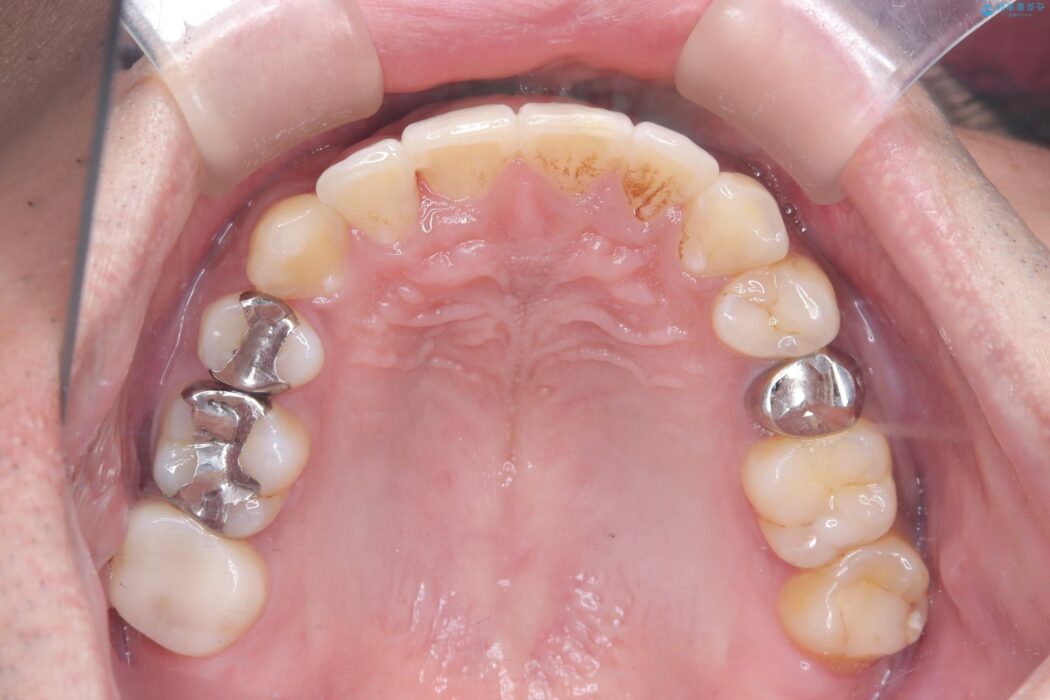

目立つ八重歯と下の歯の凸凹を治したい

右上の八重歯と、下の歯の凸凹を治したいとご来院されました。

上顎右側第一小臼歯と下顎右側第一小臼歯を抜歯しワイヤー矯正を行いました。

噛み合わせのズレが右側で大きかった(2級)ため、右側上下2本の歯を抜歯し、ワイヤー矯正で噛み合わせを左右対称の理想的な位置に改善しました。